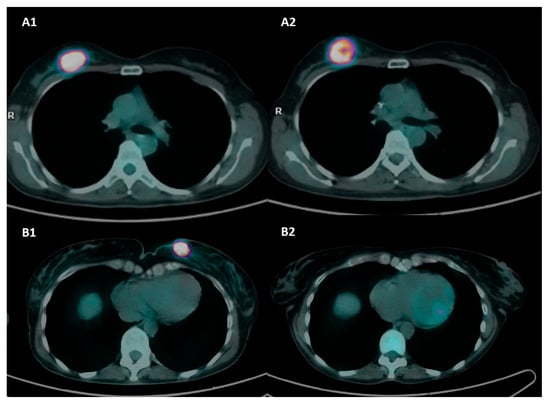

The sensitivity and specificity of preoperative PET/CT were 62.3% and 93.8%, respectively, based on the pCR/RD classification, whereas when the RCB index was considered, the sensitivity and specificity were 58.6% and 94.9%, respectively. The diagnostic performance of the qualitative analysis is presented in Supplementary Table S5. An example of a different response to NAC at preoperative PET/CT is provided in Figure 1.

Figure 1. Axial [18F]FDG-PET/CT images at baseline and preoperative assessment in two patients with triple-negative BC and different response to NAC. Patient A was a 50-year-old patient with biopsy-confirmed invasive breast cancer, G3, ER: 0%, PgR: 0%, Ki67: 80%, HER2-positive, and axillary pathological lymph nodes (stage II). Baseline PET images (A1) show a pathological nodule with intense tracer uptake in the upper external quadrant of the right breast (SUVmax 46.8). Preoperative PET images (A2) show a partial metabolic response to NAC (SUVmax 31.1). Definitive histopathology after QUART + BLS was ypT2 N1a and classified as RD and RCB-III. Patient B was a 55-year-old patient with biopsy-proven invasive breast cancer, G2, ER: 0%, PgR: 0%, Ki67: 38%, HER2-, stage II. Baseline PET images (B1) show a pathological nodule with intense tracer uptake in the upper inner quadrant of the left breast (SUVmax 44.7). Preoperative PET images (B2) show a complete metabolic response to NAC (SUVmax 1.1). Definitive histopathology after QUART + BLS was ypT0 N0 and classified as pCR and RCB-0.